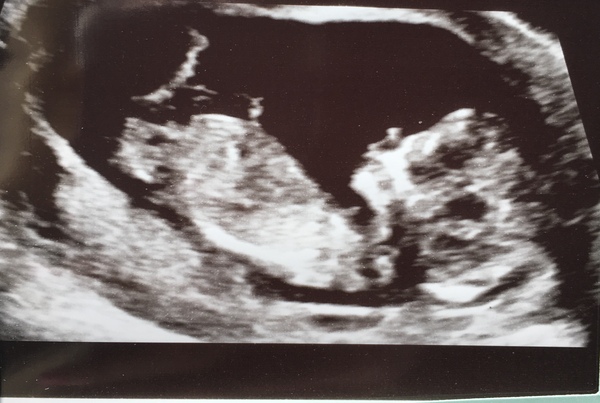

Here's my scan picture 😊 it's the nucheal fold measurement (part of the combined screening) for downs, Edwards and patau. @cobblestones

@jelliestogether what’s an NT measurement? I haven’t yet had a dating scan so wondering how that is different from previous scans where they just measure length and tell you how far along you are. Great you get another scan in 2 weeks!

Had my scan today, exactly 12 weeks but need to go back in 2 weeks as was a tiny bit too small to do the NT measurement. Bit gutting as couldn't get a proper dating scan. But was lovely to see the little thing on a screen moving around once it woke up! Plus we get to see it again in 2 weeks! But my main worries have been settled, had a heartbeat and all limbs and brain looked normal!